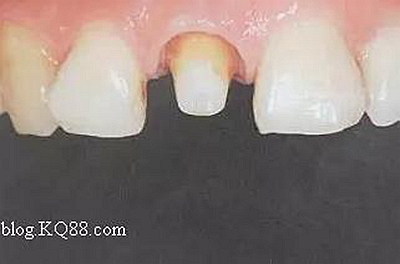

如下圖剩余的組織就過(guò)于薄弱,以后也是一個(gè)安全隱患。

2、去除暫封物。